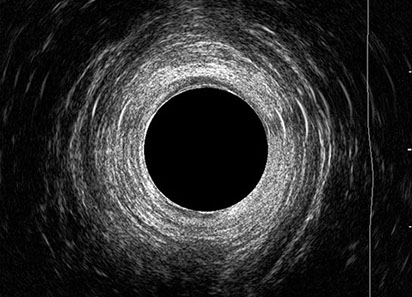

L’ecografia transanale è un esame diagnostico per immagini che consiste nell’introduzione di un trasduttore ad ultrasuoni. Le immagini qualitativamente migliori del canale anale sono ottenute usando un trasduttore rotante, montato in un manipolo rigido, che fornisce un’immagine a 360°. Con le apparecchiature più moderne è anche possibile ottenere immagini tridimensionali.

L’ecografia transanale permette di distinguere la sottomucosa che riveste il canale anale, lo sfintere anale interno, e lo sfintere anale esterno.

Proctal dispone di apparecchiatura per ecografia endoanale 3D con sonda rotante.